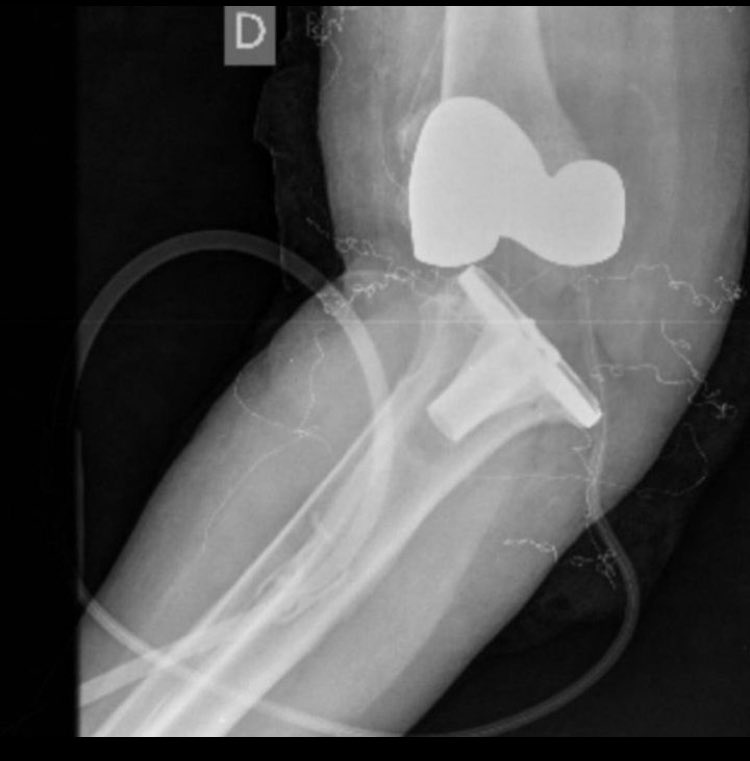

Implant ID? Is this the Zimmer one that has NOT been recalled? Currently asymptomatic